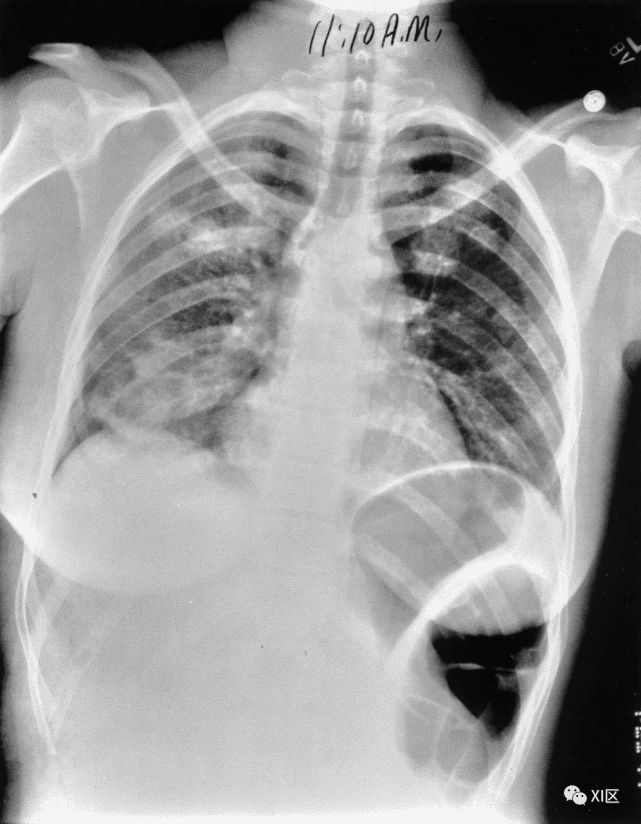

图8 20岁男子因腺病毒感染引起肺炎,伴有发热、咳嗽和呼吸困难。

(上) 最初的胸片显示左中下肺和右下肺区有不明确的斑片状实变和GGO(箭头)。同一天在叶间支气管水平(中)和肺下静脉水平(下)上获得的轴位胸部CT图像(厚度为5mm)显示不明确的斑片状GGO(箭头)和大叶实变(箭)。

Koo H J , Lim S , Choe J , et al. Radiographic and CT Features of Viral Pneumonia[J]. Radiographics, 2018, 38(3):719-739.